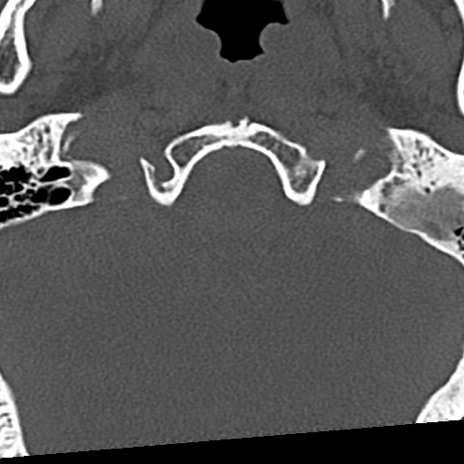

頚椎CT

冠状断像